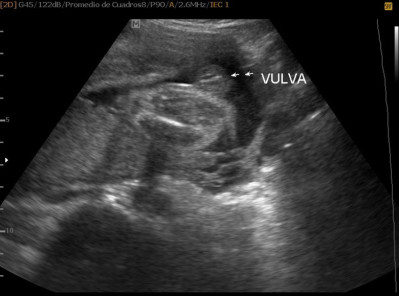

Varias ultrasonografías en 2D y 3D

Envíado por Dr. Nelson Menjívar Sarco